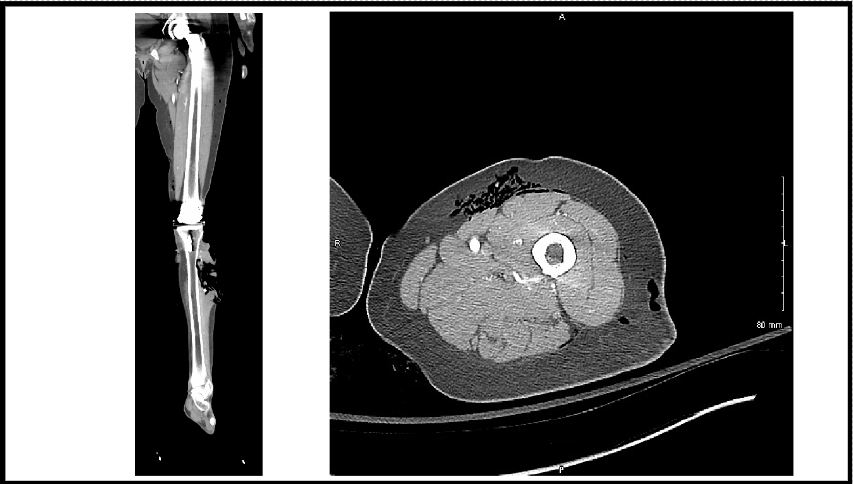

Upon arrival, she received a tetanus shot and was placed on cefepime, vancomycin, and metronidazole. Grossly, there was extensive soft tissue damage to the left forearm and hand, in addition to exposed metacarpal bones and complete amputation of the index, long, and ring fingers on the left hand. Radiographs of the wrist demonstrated a comminuted open distal ulna and a comminuted articular distal radius fracture. Moreover, the left radial and ulnar arteries signals were lost distal to the site of the wrist fracture, and the distal tissue was cold to the touch. Computed tomography scan demonstrated a Morel-Lavallée lesion on her left thigh (Figure 11).

Figure 11. Computed tomography (left) of the alligator bite to the lower leg and (right) of the Morel-Lavallée lesion on the upper thigh of case 2.